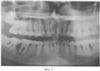

На фиг.5 представлена рентгенограмма пациента 3 до лечения.

На фиг.6 – рентгенограмма пациента 3 после лечения, проведенного без коррекции минерального обмена.

Пример 3. Больной М., 1964 года рождения, обратился на кафедру терапевтической стоматологии ФПДО Московского государственного медико-стоматологического университета с жалобами на подвижность зубов, затрудненное пережевывание пищи, боль в деснах при чистке зубов и приеме пищи. Ранее лечился у пародонтолога в поликлинике по месту жительства. Лечение заключалось в снятии зубных отложений, проведении противовоспалительной и антимикробной терапии, протезировании. Практически здоров. Профессиональных вредностей нет, аллергию и гепатит отрицает.

Осмотр полости рта. Слизистая оболочка десны отечна, гиперемирована с синюшным оттенком, при пальпации выделяется гнойный экссудат в области всех зубов. Подвижность зубов II-III степени. Жевательная группа зубов на верхней челюсти удалена по поводу пародонтита. При зондировании в области фронтальных зубов верхней и нижней челюсти определяются пародонтальные карманы глубиной 7-8 мм. Имеется мелкое преддверие полости рта со снижением уровня прикрепленной десны за счет множественных рецессий. Гигиена полости рта удовлетворительная. Наличие обильных поддесневых зубных отложений. Прикус ортогнатический.

Данные рентгенологического исследования. На ортопантомограмме верхней и нижней челюстей определяется убыль костной ткани межальвеолярных перегородок за счет резорбции на 1/2 и более длины корня в области зубов верхней челюсти и в пределах 1/2 длины корня в области нижних зубов.

Данные лабораторных исследований. Клинический анализ крови в норме. ПТГ=55,6 пг/мл, кальцитонин 2,8 нг/л, кальций общий 2,49 ммоль/л, кальций ионизированный 1,08 ммоль/л.

Диагноз: хронический генерализованный пародонтит тяжелой степени с агрессивным течением.

Больному было проведено комплексное лечение, включающее обучение гигиене полости рта, санация некачественно запломбированных каналов, снятие поддесневых зубных отложений и кюретаж пародонтальных карманов, проведение антибиотикотерапии (сумамед 250 мг – 5 дней), изготовление шинирующих конструкций и временных коронок на нижнюю и верхнюю челюсти. Проведено хирургическое лечение (лоскутная операция с остеопластикой и введением препарата Остеопласт в область вертикальных костных дефектов). Коррекция минерального обмена не проводилась. Повторное обследование проводили через 11 месяцев после начала лечения. Осмотр полости рта показал следующее: слизистая оболочка десны бледно-розового цвета, без признаков кровоточивости, глубина пародонтальных карманов в пределах 3 мм в области всех зубов. Сохранилась патологическая подвижность фронтальных зубов верхней челюсти в пределах I степени. На ортопантомограмме определяется уплотнение костной ткани межальвеолярных перегородок, восстановление кортикальной пластинки по краю альвеолярного отростка. Вертикального прироста костной ткани не отмечается.

Данные лабораторных исследований. ПТГ=54,9,4 пг/мл, кальцитонин 2,9 нг/л, кальций общий 2,43 ммоль/л, кальций ионизированный 1,08 ммоль/л.

Пример подтверждается рентгенограммами, выполненными до лечения – фиг.5 и после лечения – фиг.6.